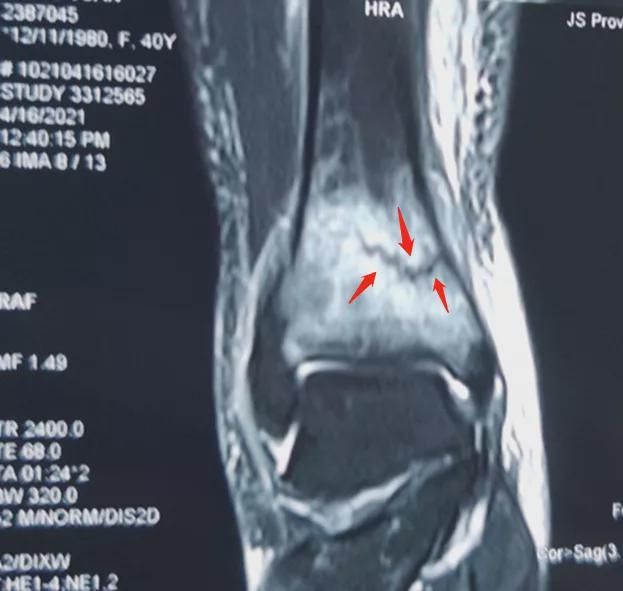

核磁共振检查结果显示,张女士小腿骨有一条清晰可见的裂纹,也就是骨折线,诊断为应力性骨折,也叫疲劳骨折。